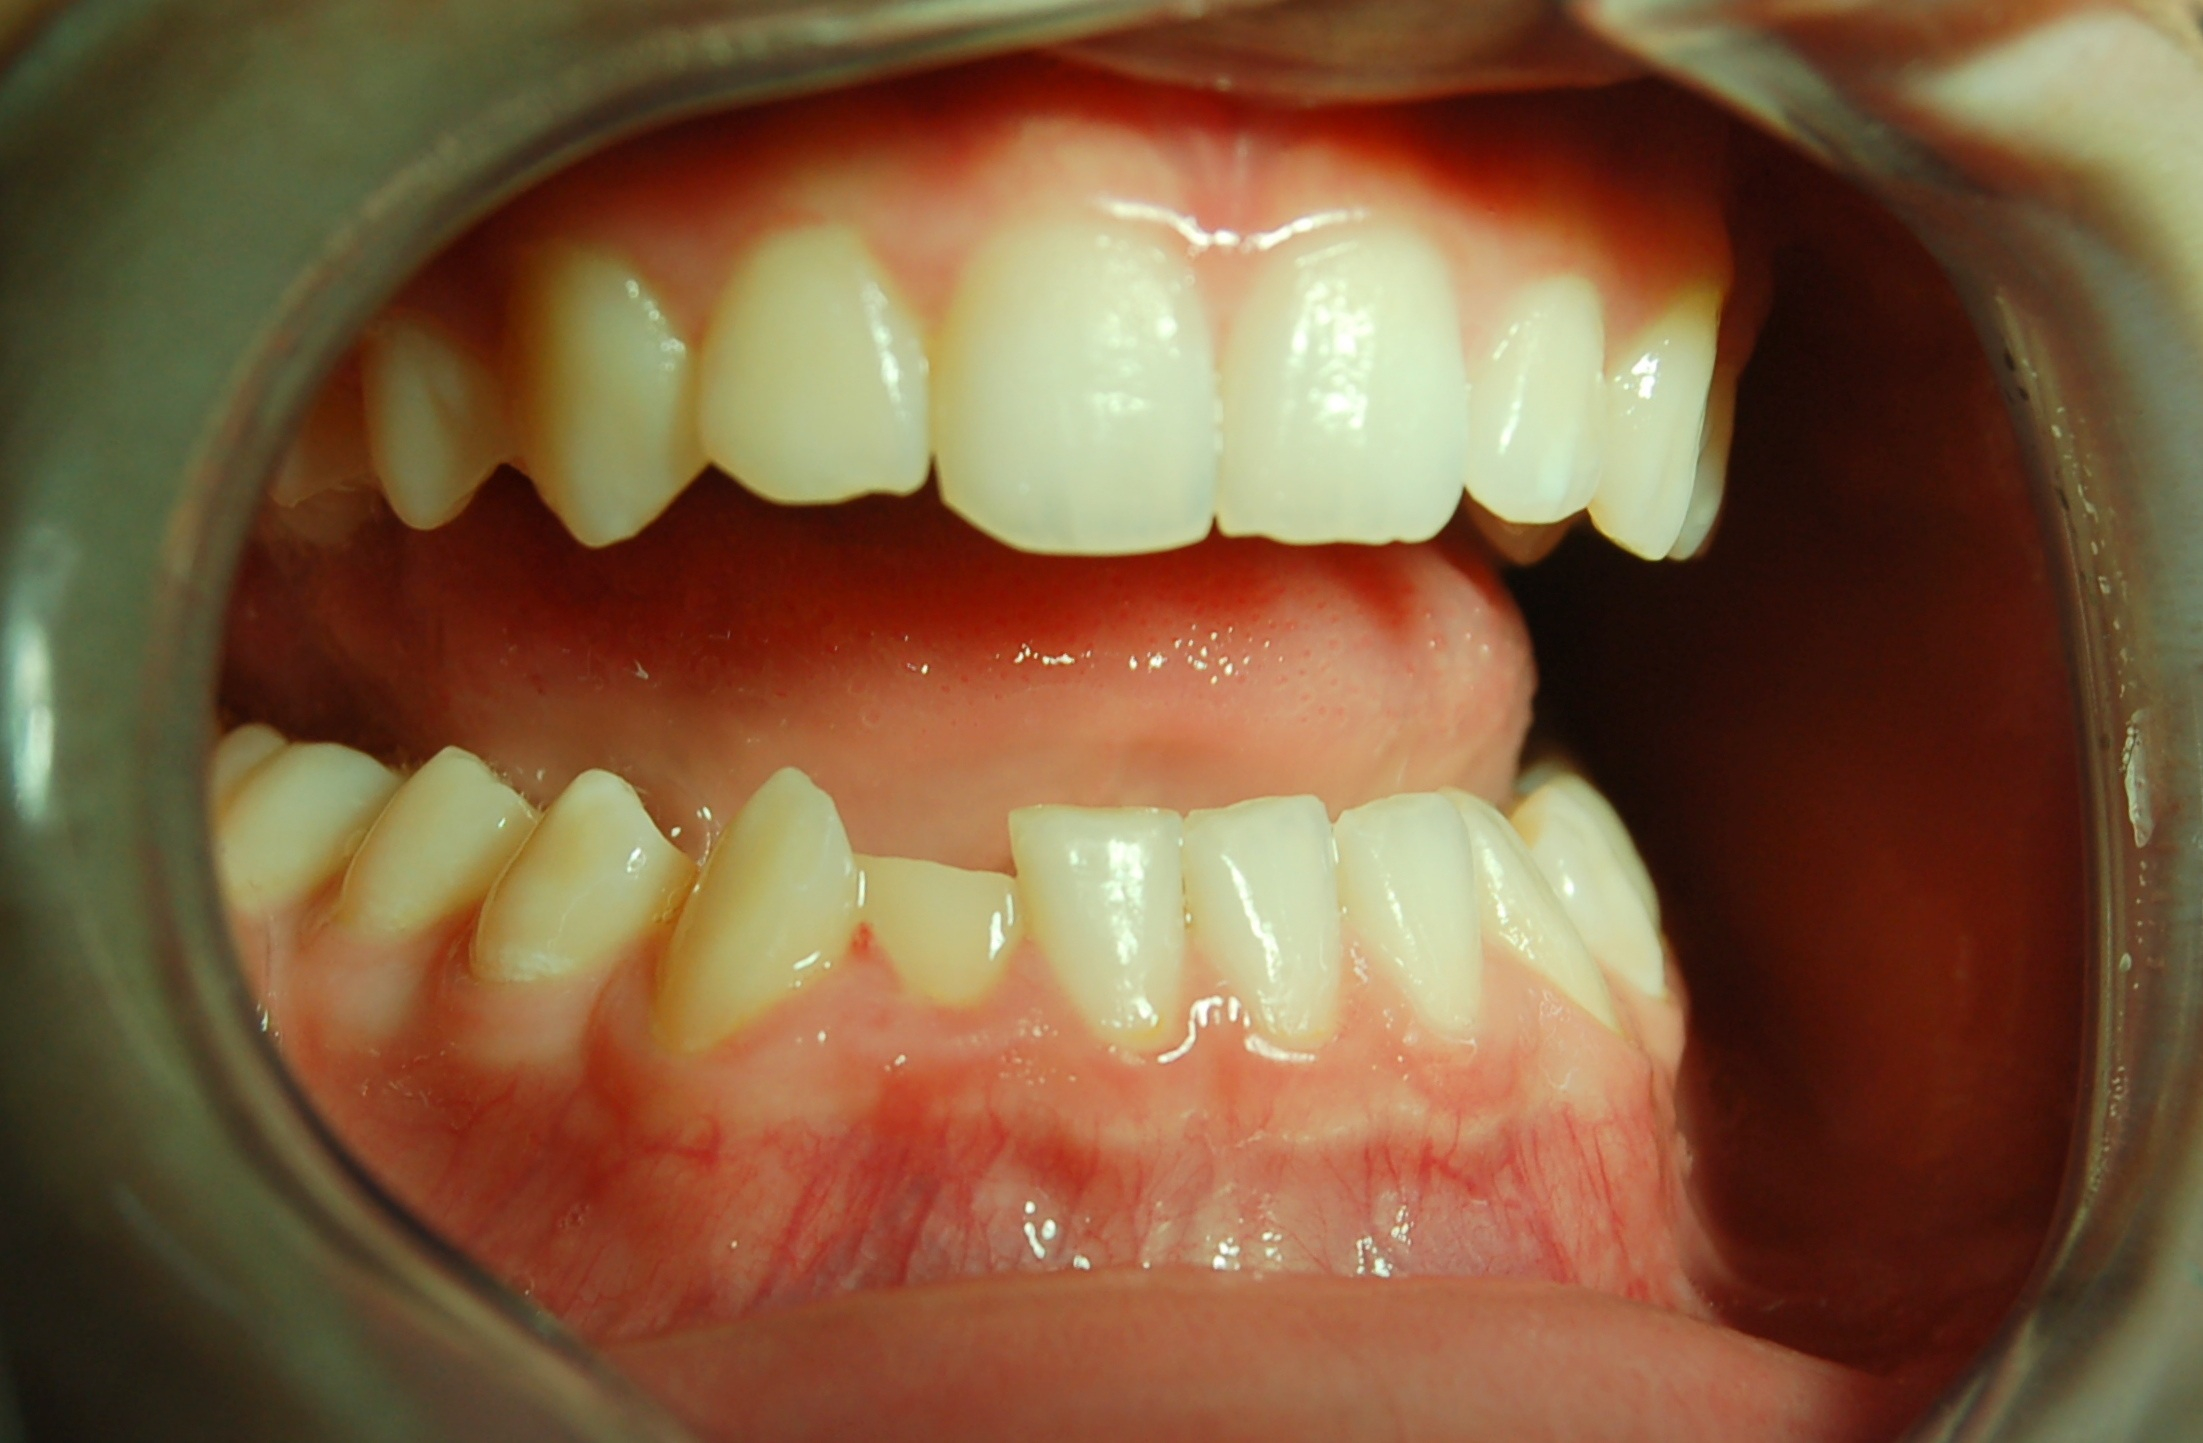

Il paziente di 13 anni mostra una lesione trasversale dell'incisivo laterale inferiore di destra, in seguito ad un trauma sportivo.

Queste lesioni sono molto frequenti in questa fascia di età e risulta fondamentale avere un approccio che sia il più conservativo possibile.

Anni fa un caso di questi veniva trattato con l'ausilio di perni dentinali o addirittura devitalizzando e ricostruendo il dente con un perno canalare.

Oggi, grazie ai progressi dell'odontoiatria adesiva si può ottenere un risultato esteticamente eccellente con un danno biologico minimo.

Una volta lucidati i margini del frammento si eseguono le procedure adesive e quindi si utilizza del composito adeguatamente riscaldato per la cementazione.

Il risultato è estremamente soddisfacente.